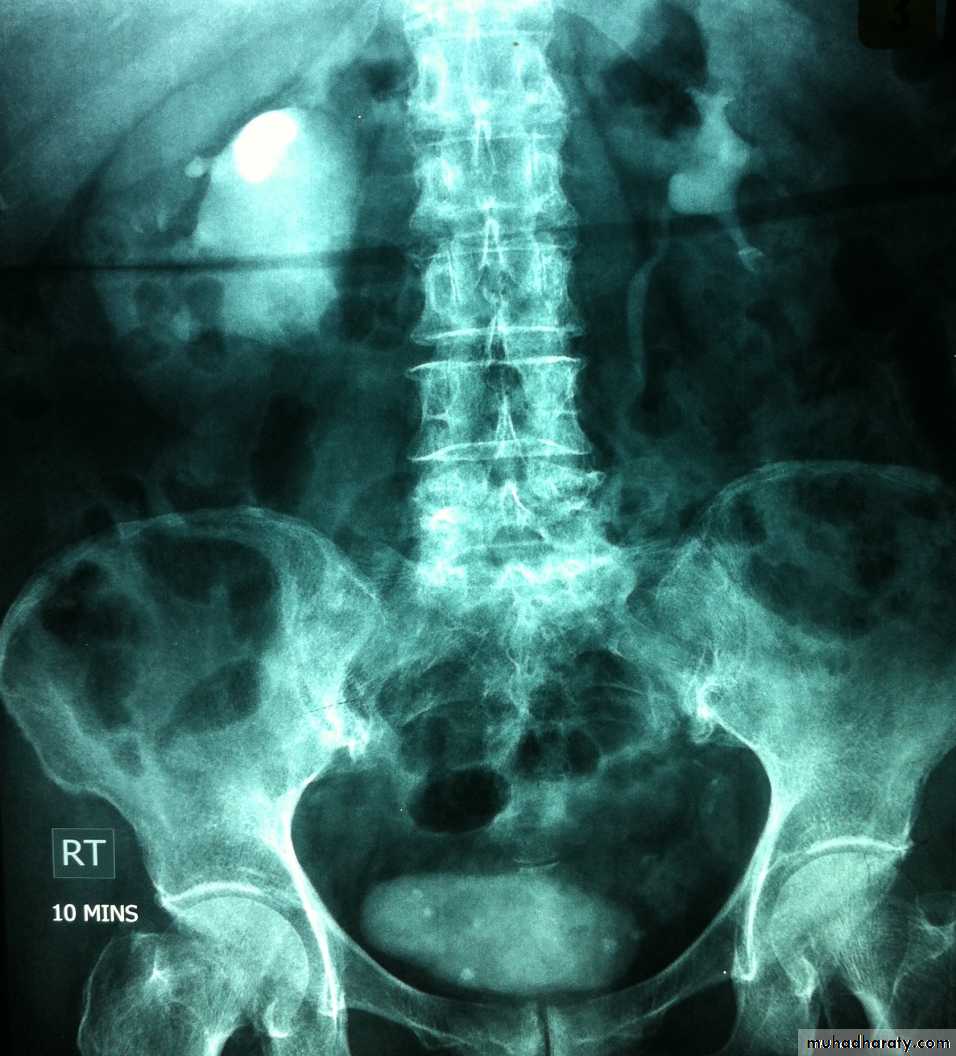

Poly cystic disease

Adult type

Present after the third decade of life , Familial.

Renal parenchyma is replaced by numerous cysts containing fluid , The cysts are of variable size ,

Clinically renal colic, loin mass , heamaturia and hypertension, Renal tissue interposed between the cysts after time dssimcted ended with renal failure

Almost bilateral.

IVU

Large kidney .

Lobulated out-line.

Distortion of pelvi- calyceal system depend on cyst size, number and position.

In advanced cases there is elongation and stretching of minor and major calyces ( spider leg).

In advanced cases IVU shows non-functioning kidney .